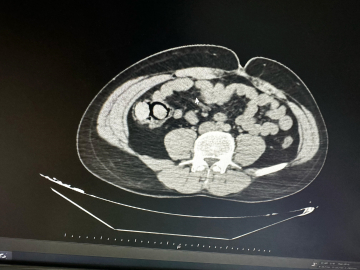

Aziz ÖNAL/ BİNGÖL, (DHA)- BİNGÖL’de polis ekiplerince düzenlenen uyuşturucu operasyonunda midelerinde 10 parça halinde 113 gram metamfetamin tespit edilen 2 şüpheli, tutuklandı. İl Emniyet Müdürlüğü Narkotik Suçlarla Mücadele Şube Müdürlüğü ekipleri tarafından gerçekleştirilen operasyonda, uyuşturucu ticareti yapmak üzere kente otobüsle geldiği bilgisine ulaşılan 2 şüpheli gözaltına alındı. Şüphelilerin hastanede yapılan muayenelerinde, midelerinde toplamda 10 parça halinde 113 gram metamfetamin maddesi ele geçirildi. Şüphelilerin midelerindeki uyuşturucu paketleri, hastanede yapılan işlemle çıkarıldı. Emniyetteki işlemlerinin ardından adliyeye sevk edilen şüpheliler, sevk edildikleri adliyede çıkarıldıkları mahkemece tutuklanarak cezaevine gönderildi.(DHA)